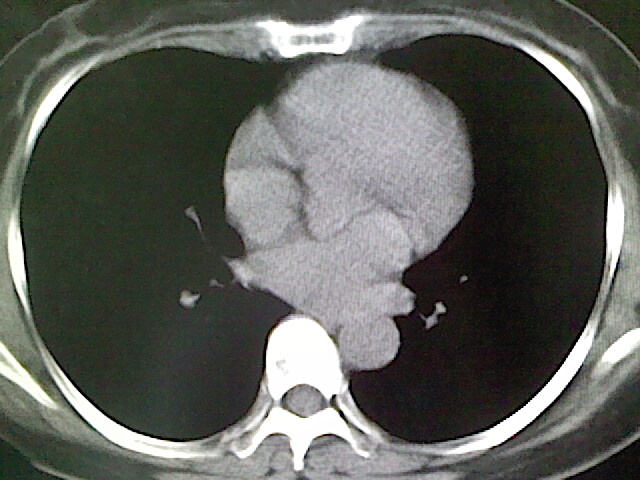

女,52岁,咳嗽,咳痰多日

左下肺陈旧纤维索条!

左肺舌段炎性改变

我见过几例,为炎症后纤维条索

慢性炎症后改变

考虑慢性炎性病灶粘连牵拉改变。

左肺舌叶纤维锁条病变。

左肺上叶下舌段炎症并局部胸膜反应。

左肺舌叶纤维索条影。

左肺舌叶段陈旧性病变

左肺舌段炎性反应。片子的质量太不好了。

左肺舌段炎性

炎性改变

左肺舌叶纤维索条影